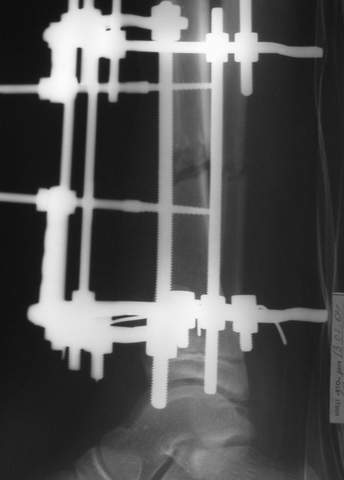

МТ мы используем, конечно, не только на голени. В прилагаемом примере у парня при поступлении была наружная ротация 40 гр. и "полумертвый" коленный сустав. Можно был бы, конечно, до конца использовать полную компоновку. Но для того он и есть метод выбора.